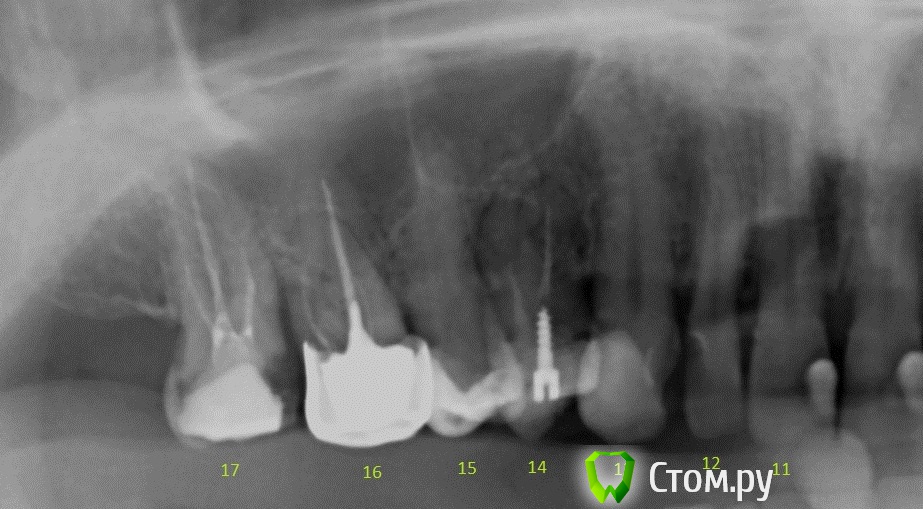

Вася123 Опубликовано 27 марта, 2014 Поделиться Опубликовано 27 марта, 2014 Добрый деньПоделитесь пожалуйста мыслями. Интересует только то что на фото. На фото изображена верхняя челюсть, правая часть, зубы 13 - клык, живой, пломба14,- штифт, пломба15,- пломба16, - вкладка + коронка17. - пломба врач одной из частных клиник рекомендует:14 зуб удалить, т.к. именно над ним он заметил воспаление костной ткани13 и 15 депульпация и обточка то ли под мост то ли под протез на место 14го16 зуб не удалять, тк воспаления нет, а просто перепломбировать каналы + замена коронки17 зуб - под коронку врач другой частной клиники рекомендует16 зуб удалить и тоже что то про протезы советовал Мало того что это все стоит очень прилично, у меня нет уверенности что сделают все это:- во первых по правильной схеме,- во вторых качествено..- не навредят еще больше Подскажите насколько адекватно мнение врачей ? Нужно ли вобще чтото удалять?Если и правда есть воспаление костной ткани - насколько это страшно и что с этим делать? Ссылка на комментарий

DmitrySH Опубликовано 27 марта, 2014 Поделиться Опубликовано 27 марта, 2014 Тут конечно смотреть в полости рта, что там с зубом 14. То, что вокруг зуба изменения - еще не повод для удаления. Примерный план такой:17, 16, 14 ревизия каналов и покрытие коронками, 15, 13 лечение и восстановление исходя из размера поражения Если 14 удаляется, то имплантация. Не надо мосты городить. P.S. все остальные зубы верхней челюсти и нижние моляры тоже требуют к себе внимания. Заниматься частичным латанием дыр уже поздно, требуется комплексная реабилитация Ссылка на комментарий

DmitrySH Опубликовано 28 марта, 2014 Поделиться Опубликовано 28 марта, 2014 Не могли бы Вы про остальные зубы (если из снимка чтото можно понять конечно) рассказать что делать (по номерам)?? 11, 21 - лечение кариеса, (коронки ?)22 - вкладка и коронка23 - лечение кариеса24 - Неважно выглядит на снимке, нужно смотреть в полости рта. 26,37 - ревизия каналов, кладка и коронка38 - удаление36,47 - Пломба или керамическая накладка/коронка ( после осмотра в полости рта)48 - ? тоже нужно смотреть как-то так Ссылка на комментарий